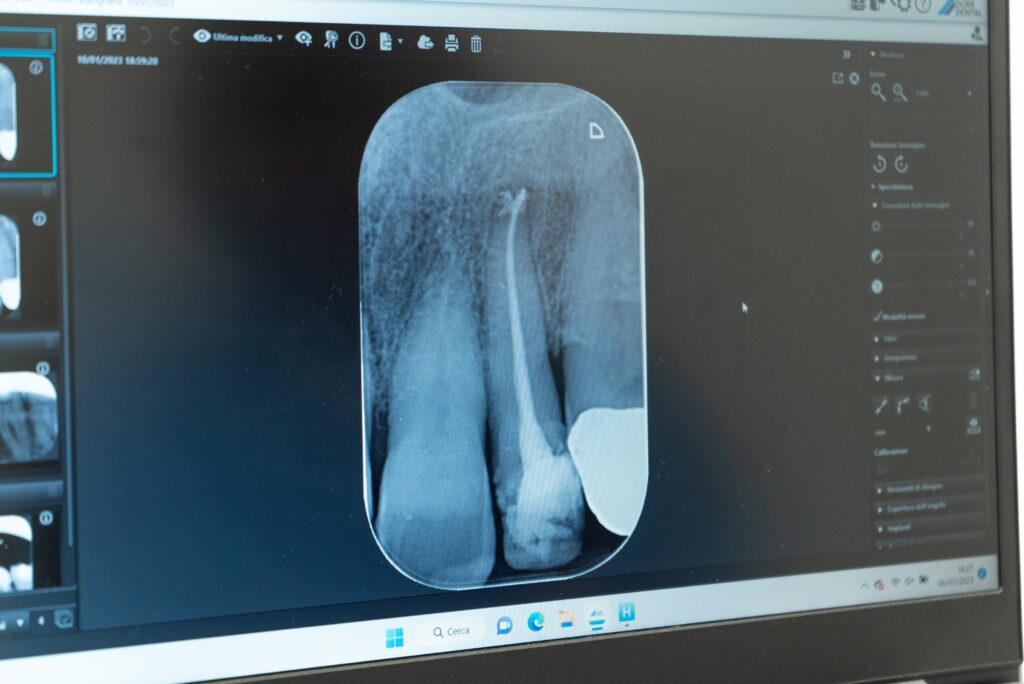

Negli ultimi anni l’endodonzia ha subito molti progressi con l’ingresso nel mercato di strumenti meccanici rotanti in nichel-titanio che aumentano drasticamente il successo della terapia e dei risultati a lungo termine. La terapia deve essere eseguita assolutamente in un campo asciutto e privo di contaminazione, utilizzando un foglio di lattice, chiamato diga di gomma, isolando così il singolo dente dal resto della bocca. Dopo aver asportato completamente il nervo passando all’interno dei canali con una sequenza mirata di strumenti, si sigillano alla lunghezza corretta le radici dei denti con coni formati da un materiale di gomma caldo chiamato guttaperca.

Per ritrattamento canalare si intende il rifacimento di una devitalizzazione. Questo avviene quando in precedenza non è stato sigillato completamente il canale oppure quando per cause batteriche si crea un’infezione cronica all’apice della radice, che può causare un ascesso. La tecnica prevede la rimozione del materiale precedente, la disinfezione con lavaggi del canale radicolare, che infine verrà sigillato nuovamente in maniera corretta per tutta la sua lunghezza.